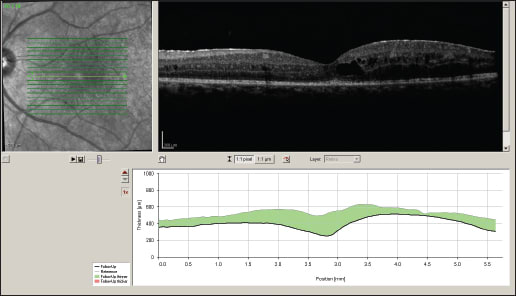

Two months after implant placement OS, the right eye was implanted. VA was 20/200 OD and 20/60 OS at that time. Four weeks after implantation OD, VA improved to 20/60 OD, and then to 20/40 OD eight weeks later (Figure 3). OCT nine months later showed dramatic resolution of CME (Figure 4). The pre-existing PSC cataract progressed. Phacoemulsification surgery with in-the-bag IOL implantation was performed OS 11 months after Retisert implantation in that eye. Vision improved from 20/80 to 20/50 after the surgery.

Figure 4. OCT of the left eye (upper image) and right eye (lower image) 14 months after initial presentation.